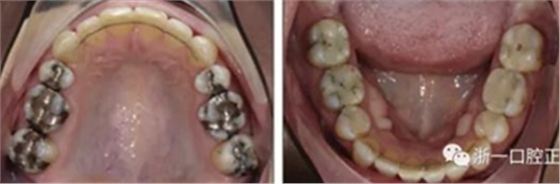

患者曾行正畸治療,現(xiàn)覺(jué)笑容不美觀前來(lái)就診?;颊哒嬗^及側(cè)貌示下頜發(fā)育不足,偏高角,唇閉合不全。上下頜中線(xiàn)齊。覆合、覆蓋4毫米。磨牙關(guān)系及尖牙關(guān)系II類(lèi)。上頜擁擠度4mm,下頜擁擠度6mm。4顆第一前磨牙在第一次正畸治療時(shí)已拔除。上下牙弓呈尖圓型,牙弓狹窄。

因此最終,我們決定采用手術(shù)輔助快速擴(kuò)弓進(jìn)行上下頜擴(kuò)弓,上頜行腭中縫切開(kāi)術(shù)、下頜行正中劈開(kāi)后使用hyrax擴(kuò)弓器進(jìn)行擴(kuò)弓。擴(kuò)弓完成后再使用固定矯治器進(jìn)行矯正。

擴(kuò)弓保持8周后,除擴(kuò)弓器影響牙外粘接托槽,使用0.014鎳鈦絲進(jìn)行排齊、整平。旋轉(zhuǎn)停止后3個(gè)月拆除擴(kuò)弓器,全口粘接托槽,使用0.016niti繼續(xù)排齊整平。佩戴可摘保持器,保持上頜寬度。在使用至0.018x0.018niti7周,徹底排齊整平后,使用大弓型的0.016x0.022不銹鋼絲,繼續(xù)維持原有寬度,同時(shí)停止使用可摘保持器。掛II類(lèi)牽,糾正磨牙關(guān)系,使用鏈圈關(guān)閉散在間隙,少量使用IPR去除局部前牙的黑三角。術(shù)后9個(gè)月拍全景示,牙根平行度可,再無(wú)其他牙根出現(xiàn)問(wèn)題。1年7個(gè)月后治療結(jié)束。上下頜3-3舌側(cè)保持器+哈雷氏保持器進(jìn)行保持。